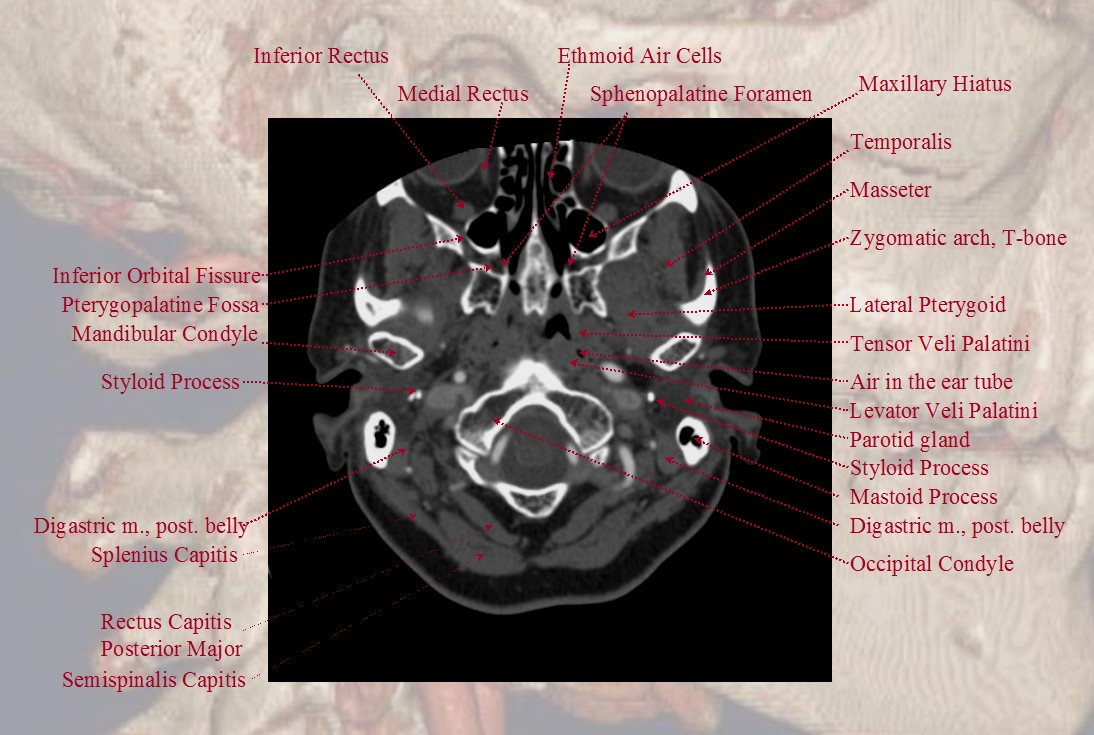

In this article, we shall look at the anatomy of the bones of the skull. Axial Ct Bone Window Of Skull Base From Inferior To Superior Aspect Download Scientific Diagram

Ct scan of elderly man with old occipital infarct. Occipital bone and skull base development is complex and derives from four occipital sclerotomes. We'll look at the bones around it, the connections between these . In this article, we shall look at the anatomy of the bones of the skull. Of the basilar occipital bone at its junction with the sphenoid bone. Anatomy, head and neck, occipital bone, artery, vein, and nerve. The clivus (latin for slope) is a bony part of the cranium at the skull base,. A normal variant of the cranial bones, of no significance to the surrounding anatomy or pathology.